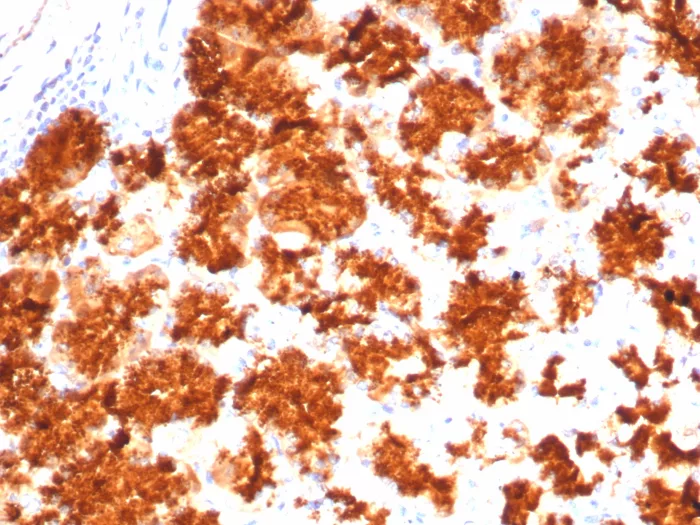

Formalin-fixed, paraffin-embedded human adrenal gland stained with Interleukin-2 (IL-2) Mouse Monoclonal Antibody (IL2/4983). HIER: Tris/EDTA, pH9.0, 45min. 2°C: HRP-polymer, 30min. DAB, 5min.